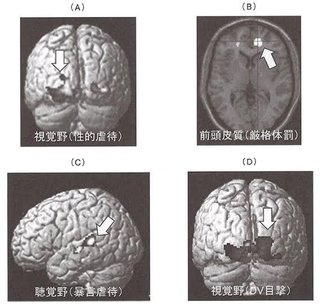

幼少気の「不適切な育児」で子どもの脳は物理的に変形してしまう